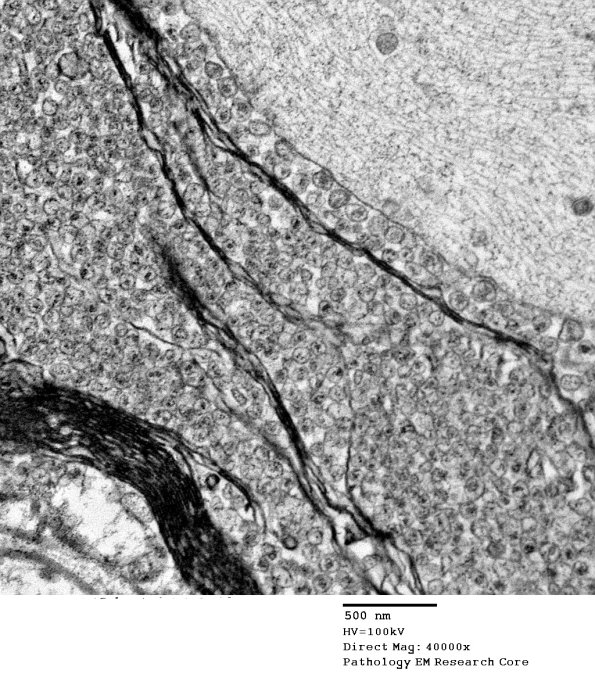

19C7 Artifact, vesicular myelin, spinal root EM 035A - Copy

Higher magnification of image #19C4. (electron micrograph)